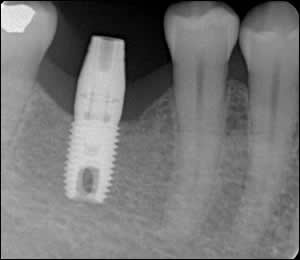

Fig 4: Guided tissue regeneration with platelet rich plasma resulted in complete bone fill of the extraction socket and intimate contact of alveolar bone with the implant surface.